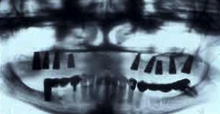

The regeneration of the jawbone is, in most cases, essential for implant placement. When a tooth is removed, the remaining bone atrophies. Atrophy increases with the years. This makes the placement of an implant difficult or impossible without first regenerating the bone

Our long experience in the regeneration of bone published in articles and dental conferances allowed us to recreate for our patients fixed dentitions instead of denture teeth.